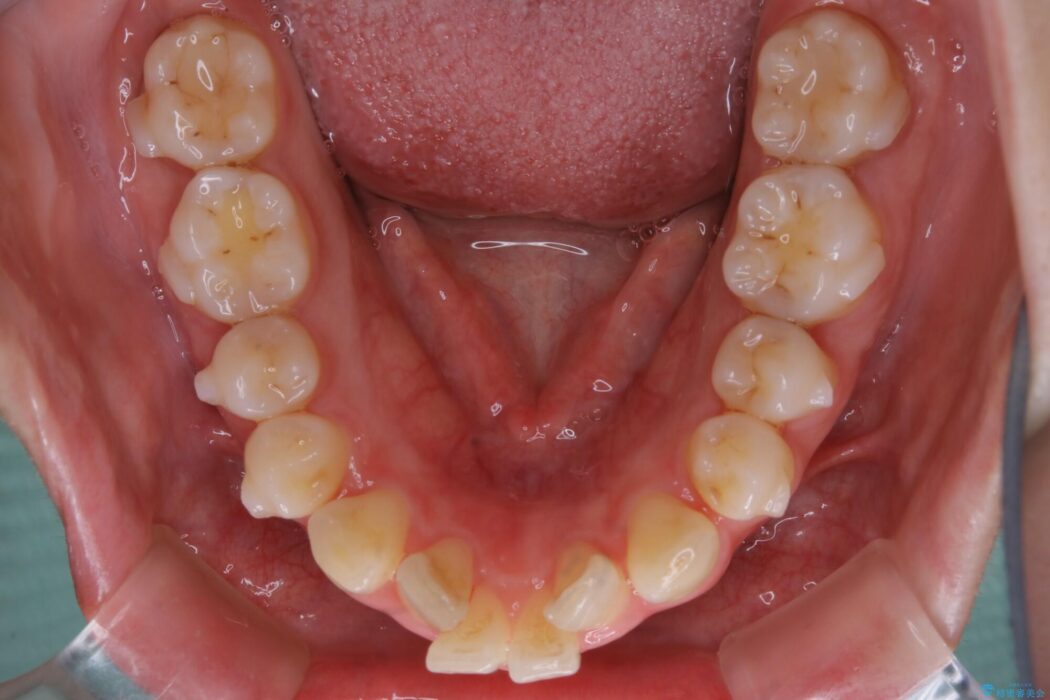

口ゴボに加えて歯列のガタガタを改善したいと来院されました。

患者様のご希望によりインビザライン装置での治療を行いました。

インビザラインは歯を後ろへ動かす動き、非抜歯での矯正治療が得意なため、ワイヤー装置では難しいケースでも対応できる場合があります。

矯正治療において歯並びを整えるためにはスペースが必要になります。

抜歯・歯列幅の拡大・IPR(歯と歯の間を少し削って小さくする)・歯の後方移動などでそのスペースを確保します。

程度にもよりますが口元を下げる治療というと抜歯治療を思い浮かべると思いますが、インビザラインは抜歯をせずとも他の3種類の方法を効率よく活用し治療ができます。